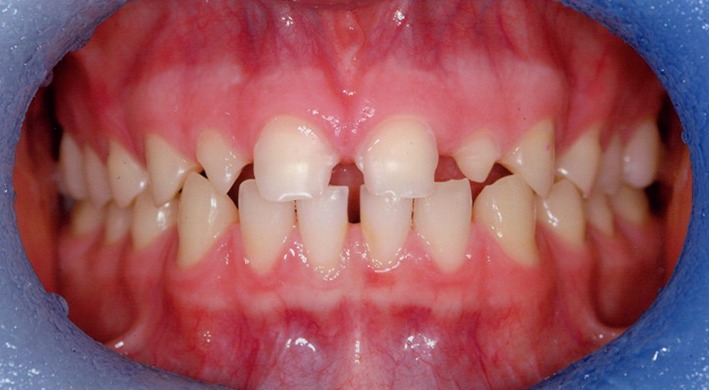

A 17 year old patient, also referred to a teaching hospital, was complaining of the appearance of his anterior teeth due to erosion from a history of excessive intake of carbonated drinks (Coca Cola). On presentation, he had completely stopped his intake of carbonated drinks over the previous 12 months. Prior to that, however, he consumed at least one litre of carbonated drinks per day. He presented with severe wear of his upper teeth (Fig. 10) together with wear affecting the occlusal surfaces of his posterior teeth. He had excellent oral hygiene and in addition to brushing with a fluoride toothpaste twice daily, he was also using a fluoride mouth rinse.

Fig. 10.

Pre-operative buccal view